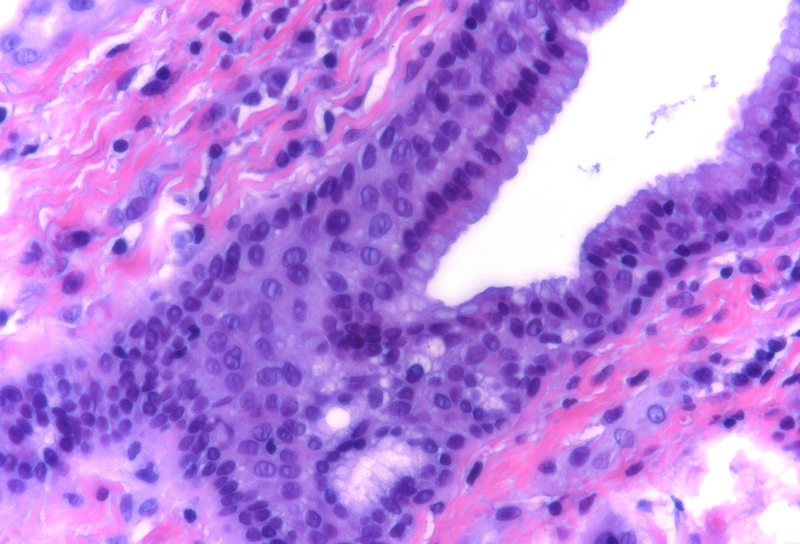

Histological examination disclosed a hybrid cyst lining epithelium, composed of a luminal layer of columnar cells with slightly basophilic cytoplasm and signs of mucin production, while slightly darker cuboidal cells without specific differentiation were present basally (Panel B-C). The cells exhibited mild nuclear irregularities, but no true dysplastic or malignant features were observed. The fibrotic cyst wall contained no skin adnexal structures, neural tissue, smooth muscle bundles or specific stroma. Immunohistochemical studies showed strong and diffuse reactivity for cytokeratin 7 of both epithelial layers (Panel D). In addition, the basal epithelial cell layer demonstrated immunoreactivity for cytokeratin 5/6 (Panel E) and p40 (Panel F). No immunohistochemical reactivity was observed for CDX2, CK20, PAX8, estrogen and progesterone receptors. Based on the morphological and immunohistochemical features, the diagnosis of a benign cyst lined by anal gland epithelium (“anal gland/duct cyst”) was made.